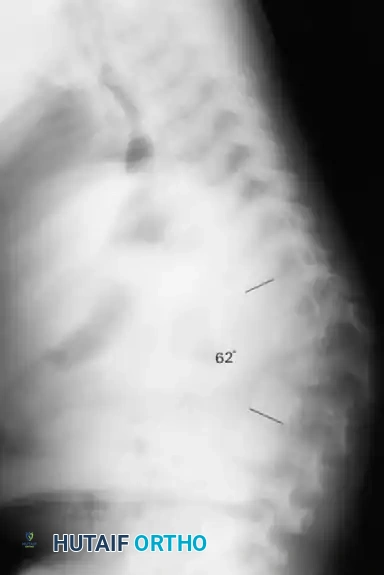

Fig. 38-219 A, Preoperative lateral radiograph of a pediatric patient with achondroplasia demonstrating severe, rigid thoracolumbar kyphosis.

Fig. 38-219 B & C, Postoperative anteroposterior and lateral radiographs demonstrating successful spinal arthrodesis with pedicle screw instrumentation, restoring sagittal balance without neurological compromise.